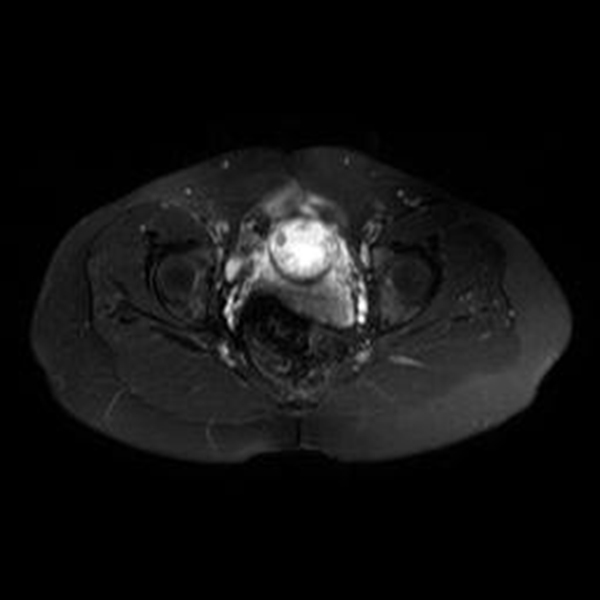

Se realizó una RNM (Philips 1.5 Tesla) que permitió confirmar el diagnóstico de EEC (figuras 5 a 8).

Figura 7A Imágenes de RMN potenciadas en T2 con supresión de la grasa. A) Plano axial y B) Plano coronal, donde se identifica el saco gestacional como una estructura quística con tejido fetoplacentario en su interior y localizado en el canal cervical

Figura 7B Imágenes de RMN potenciadas en T2 con supresión de la grasa. A) Plano axial y B) Plano coronal, donde se identifica el saco gestacional como una estructura quística con tejido fetoplacentario en su interior y localizado en el canal cervical